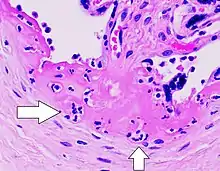

![]() Patología macroscópica de intervillositis severa, con tejido rojo oscuro y húmedo. | ||